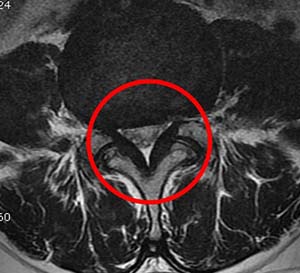

척추관 협착증 증상

허리 디스크와는차이나게 척추관 협착증은 요통보다는 다리 저림이나 당김 증상이 있어, 보행에 제일 큰 고충을 체감할 수 있습니다. 때문에 오래 걷기가 힘들고 오래 걷지 않았음에도 자꾸 주저앉게 되는 성향이 존재하는데 표준적인 협착증의 증상이라 할 수 있습니다. 기본적으로 요추부(허리)의 문제이긴 하지만 허리디스크와 다르게 허리 통증이 한결같이 동반되지는 않으며, 있더라도 허리디스크에 대조해서 적은 정도의 통증이 일어납니다.

신경을 누를 때 신경의 지배를 받는 부위로 쑤시거나 화끈거리는 통증을 호소하게 되겠습니다. 만에 하나라도 경추부(목)에 척추관 협착증이 만들어 낸다면 상/하지 모두에 영향을 줄 수 있어 다리 근력감소, 보행 불편을 나타나게 할 수 있습니다. 요추(허리) 협착증은 방사통이 엉덩이에서 시작, 다리 아래로 하향할 수 있고 이 증상을 거의 좌골신경통이라 합니다.

척추관 협착증은 척추관의 좁아짐과 신경 구조에 압력이 가해지는 것으로 인해 많은 종류의 증상이 일어날 수 있어요. 주로 통증이 띄엄띄엄 생겨날며 허리, 목, 아니면 다리 등의 부위에서 통증이 나타날수 있습니다. 뿐 와 함께 또 저림 혹은 마비가 나타날수 있기도하고 특이하게다리에서의 저림이나 마비가 예사로 보여집니다.

또한 척추관 압력으로 인해 근육 약화가 발생하여 근력이 약해지는 경우도 있다고 합니다.

이로 인해 일상적인 움직임이나 운동에 괴로움을 겪어볼 수 있어요. 척추관 협착증으로 인해 척추 구조가 변형되었다거나 신경 구조에 압력이 적용되면 동작의 제한이 등장하고 허리 부위의 증상이 다리로 통증이 방사될 수도 있고요.

신경 압박이 안좋아지면, 신경을 통한 감각 전파이 순조롭지 않아 통증과 아울러 감각 저하, 이상감각을 호소할 수 있습니다. 경추 협착증의 경우, 감각 저하가 상 / 하지 모두 일어날 수 있습니다. 신경이 견딜 수 있는 수준 마지막으로 압력이 증가하면, 하지에 근력이 감량하게 되겠습니다.

심하다 못해 나중에는 족하수, 즉 발에 힘이 안입회하고 걸을 때 발이 끌리는 현상이 생기게 되겠습니다. 허리를 앞으로 숙이면, 척추관이 넓어지고 해서 허리를 숙이고 있거나 앉아있는 것이 소홀하게 느껴지고요. 허리를 펴고 오래 걷거나 서있기 어려우며 100~200m 이상 걸으면 다리에 힘이 빠지거나 통증이 심해 쪼그려 앉아서 쉬게 되겠습니다.